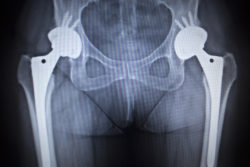

The implantation of Stryker hip implants has been associated with multiple complications. One of the most commonly reported side effects of these implants is metallosis, a kind of metal poisoning. The Stryker hip implant is considered a metal-on-metal device—that is, according to the FDA, a device in which two of its metal moving components, the metal ball and metal hip, rest directly against each other.

The specific component named in this recent Stryker LFIT litigation is the LFIT V40 femoral head. The LFIT V40 femoral head is designed to replace the natural femoral head. It sits at the end of the implant’s femoral neck and is designed to fit inside the acetabular cup, the depression within the hip bone that forms the socket of the hip joint.